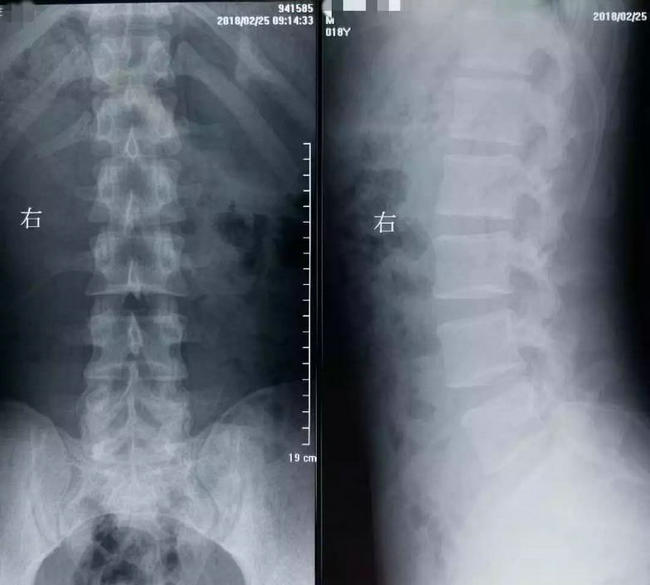

▲ 小刘在当地医院拍摄的X光片和CT片